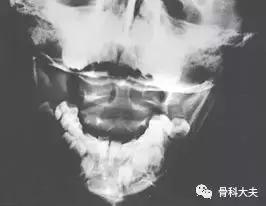

A:可以拍摄颈椎侧位及开口位X片。侧位片主要看寰齿间隙(atlanto-dens interval, ADI),正常成人<3mm,儿童因为有软骨的存在,正常<5mm,如果ADI增大,提示有寰枢椎不稳定,或增加拍摄颈椎过伸过屈位X片。大部分儿童寰枢椎半脱位的横行韧带完整,ADI正常。开口位X片可以看到寰枢椎的位置关系变化。

颈椎开口位,可看到寰枢椎位置的异常

寰齿间隙(atlanto-dens interval, ADI)